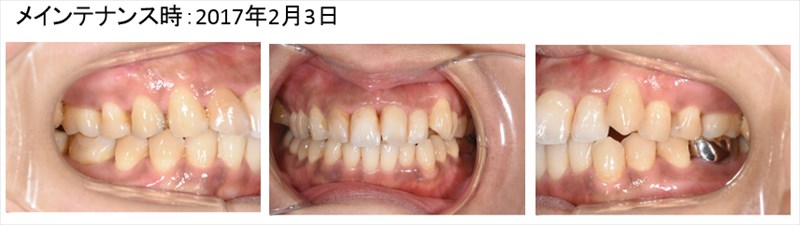

やはり歯周病が落ち着くと歯茎の色が良いです。